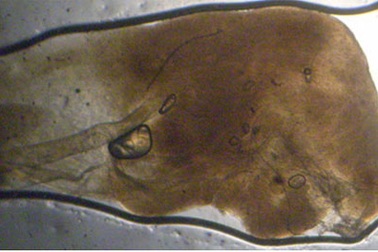

Hãi hùng sán nhái chui vào phổiTrước đây, Việt Nam chỉ ghi nhận bệnh nhân bị sán nhái ký sinh ở mắt nhưng hiện tại đã ghi nhận hai bệnh nhân bị sán nhái chui vào phổi và thành bụng mà không rõ nguyên nhân.

Cận cảnh bắt con sán 7 cm ăn não người đàn ôngBệnh viện Đại học Y Dược TP HCM vừa tiếp nhận xử trí một trường hợp hiếm gặp bị ký sinh trùng sán nhái chui lên não dẫn đến nguy cơ bại liệt.